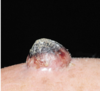

Diagnosis?

• key features?

Basal Cell Carcinoma

• Pearly appearance

• Teleangectasias

• Ulcerated